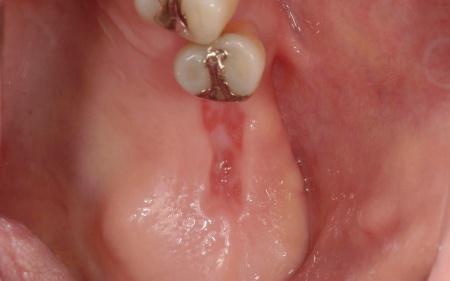

拝見したところ、左上の抜歯部周辺は歯を支える骨が溶ける「骨吸収」が進行し、隣接している歯を含めた複数の歯がひどくグラグラしており、温存が困難です。

噛み合わせも安定していなかったため、このままでは残っている歯への負担が増加し、歯の揺れやさらなる噛み合わせの悪化につながるリスクがあります。